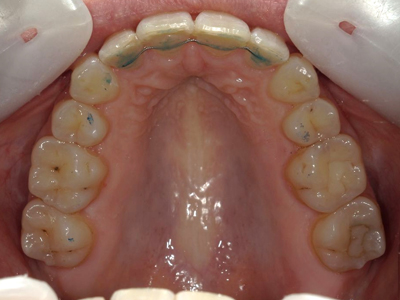

Présentation cas n°2 :